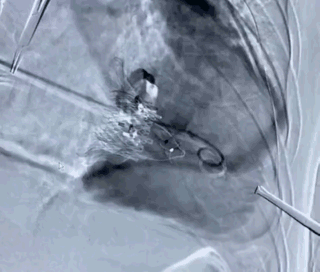

第三例患者瓣膜植入前右心室造影

第三例患者瓣膜植入后右心室造影